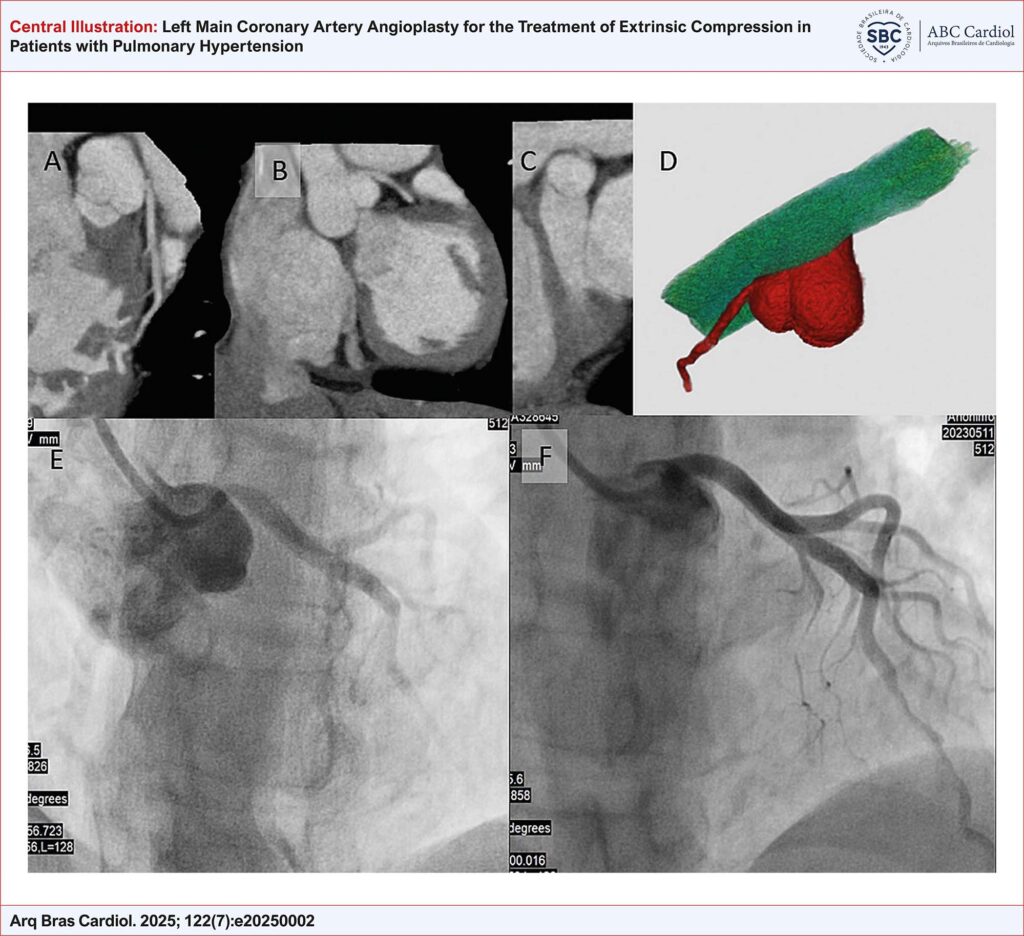

Left Main Coronary Artery Angioplasty for the Treatment of Extrinsic Compression in Patients with Pulmonary Hypertension

To assess the feasibility and impact of coronary angioplasty with stent implantation on symptom relief in patients with PH and extrinsic compression of LMCA.

This descriptive study included 12 patients with PH who were followed at the Pulmonary Circulation Outpatient Clinic of the Instituto do Coração, Hospital das Clínicas da Faculdade de Medicina da Universidade de São Paulo. All patients underwent coronary angioplasty with stent implantation to treat extrinsic compression of LMCA.

A total of 12 patients were analyzed, with a mean age of 47.9 years, predominantly with group 1 PH and under specific therapy. All procedures achieved excellent immediate results, with angina relief observed at 30 days. During a mean follow-up of 33 months, no procedure-related complications were reported, and angina symptoms remained controlled. Four patients died due to progressive heart failure.